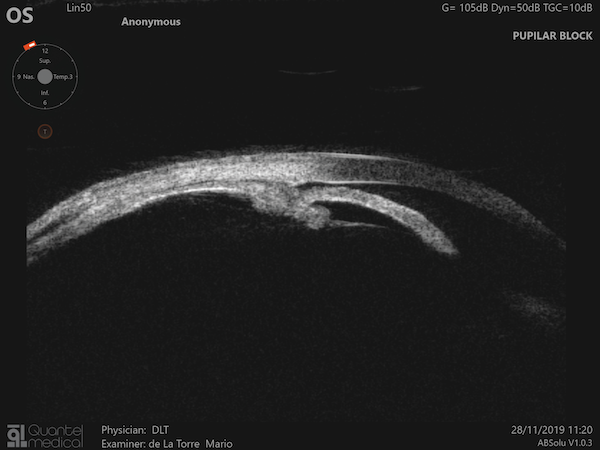

- Échographie en mode UBM : Apprenez à reconnaitre et analyser les structures de l’angle irido-cornéen.